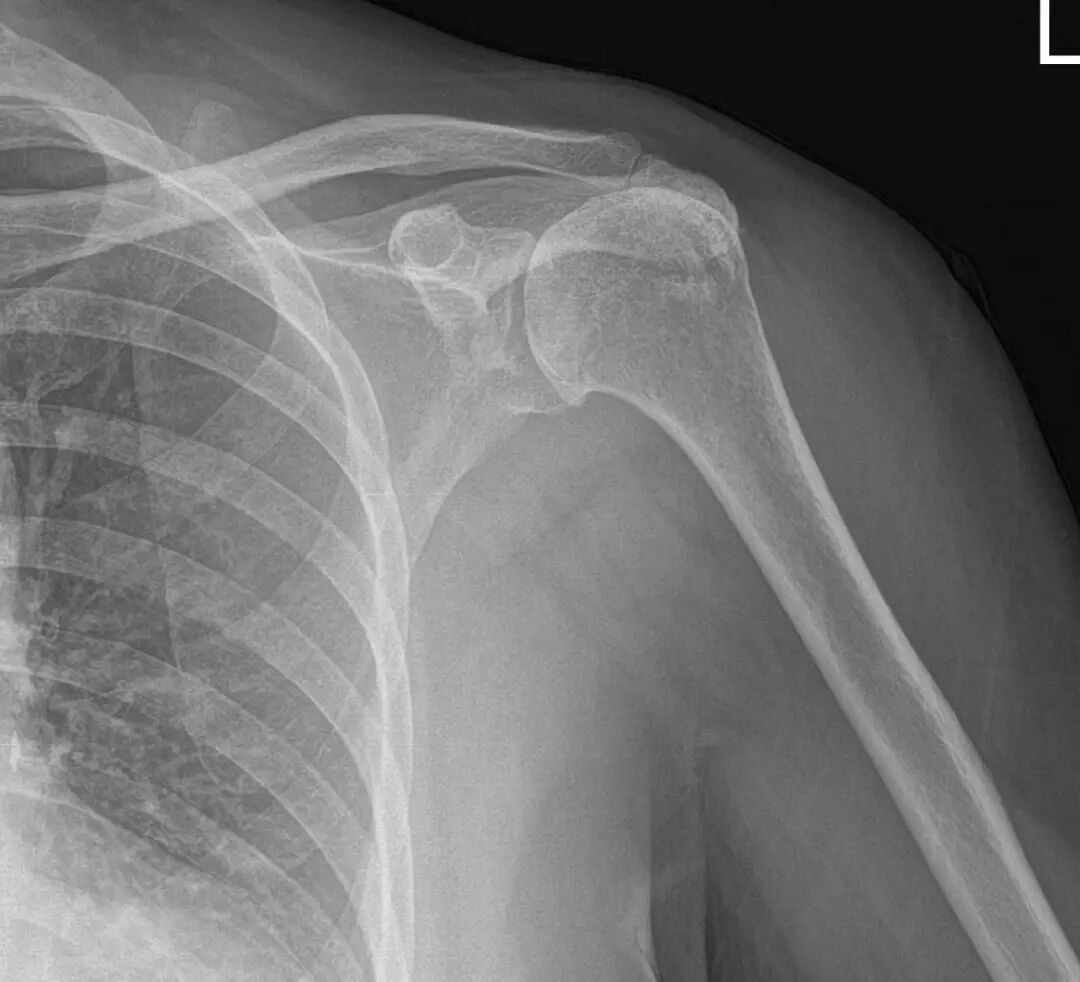

▲患者肩关节平片及MR提示巨大肩袖撕裂、肱骨头半脱位、骨关节炎

年逾古稀的施阿姨发现自己的左胳膊近几年来越来越“不来事”了,不仅疼痛逐渐加重,连抬手梳头、正常穿衣都难以完成,而膏药、按摩等治疗手段也失去以往的效果。来到同济大学附属同济医院就诊后,经过运动医学科程飚主任的详细查体,他发现施阿姨的病情并非常见的“肩周炎”,而是巨大、无法自行愈合的肩袖撕裂,并且肩部骨头之间失去缓冲,已磨损成为严重的肩关节炎。